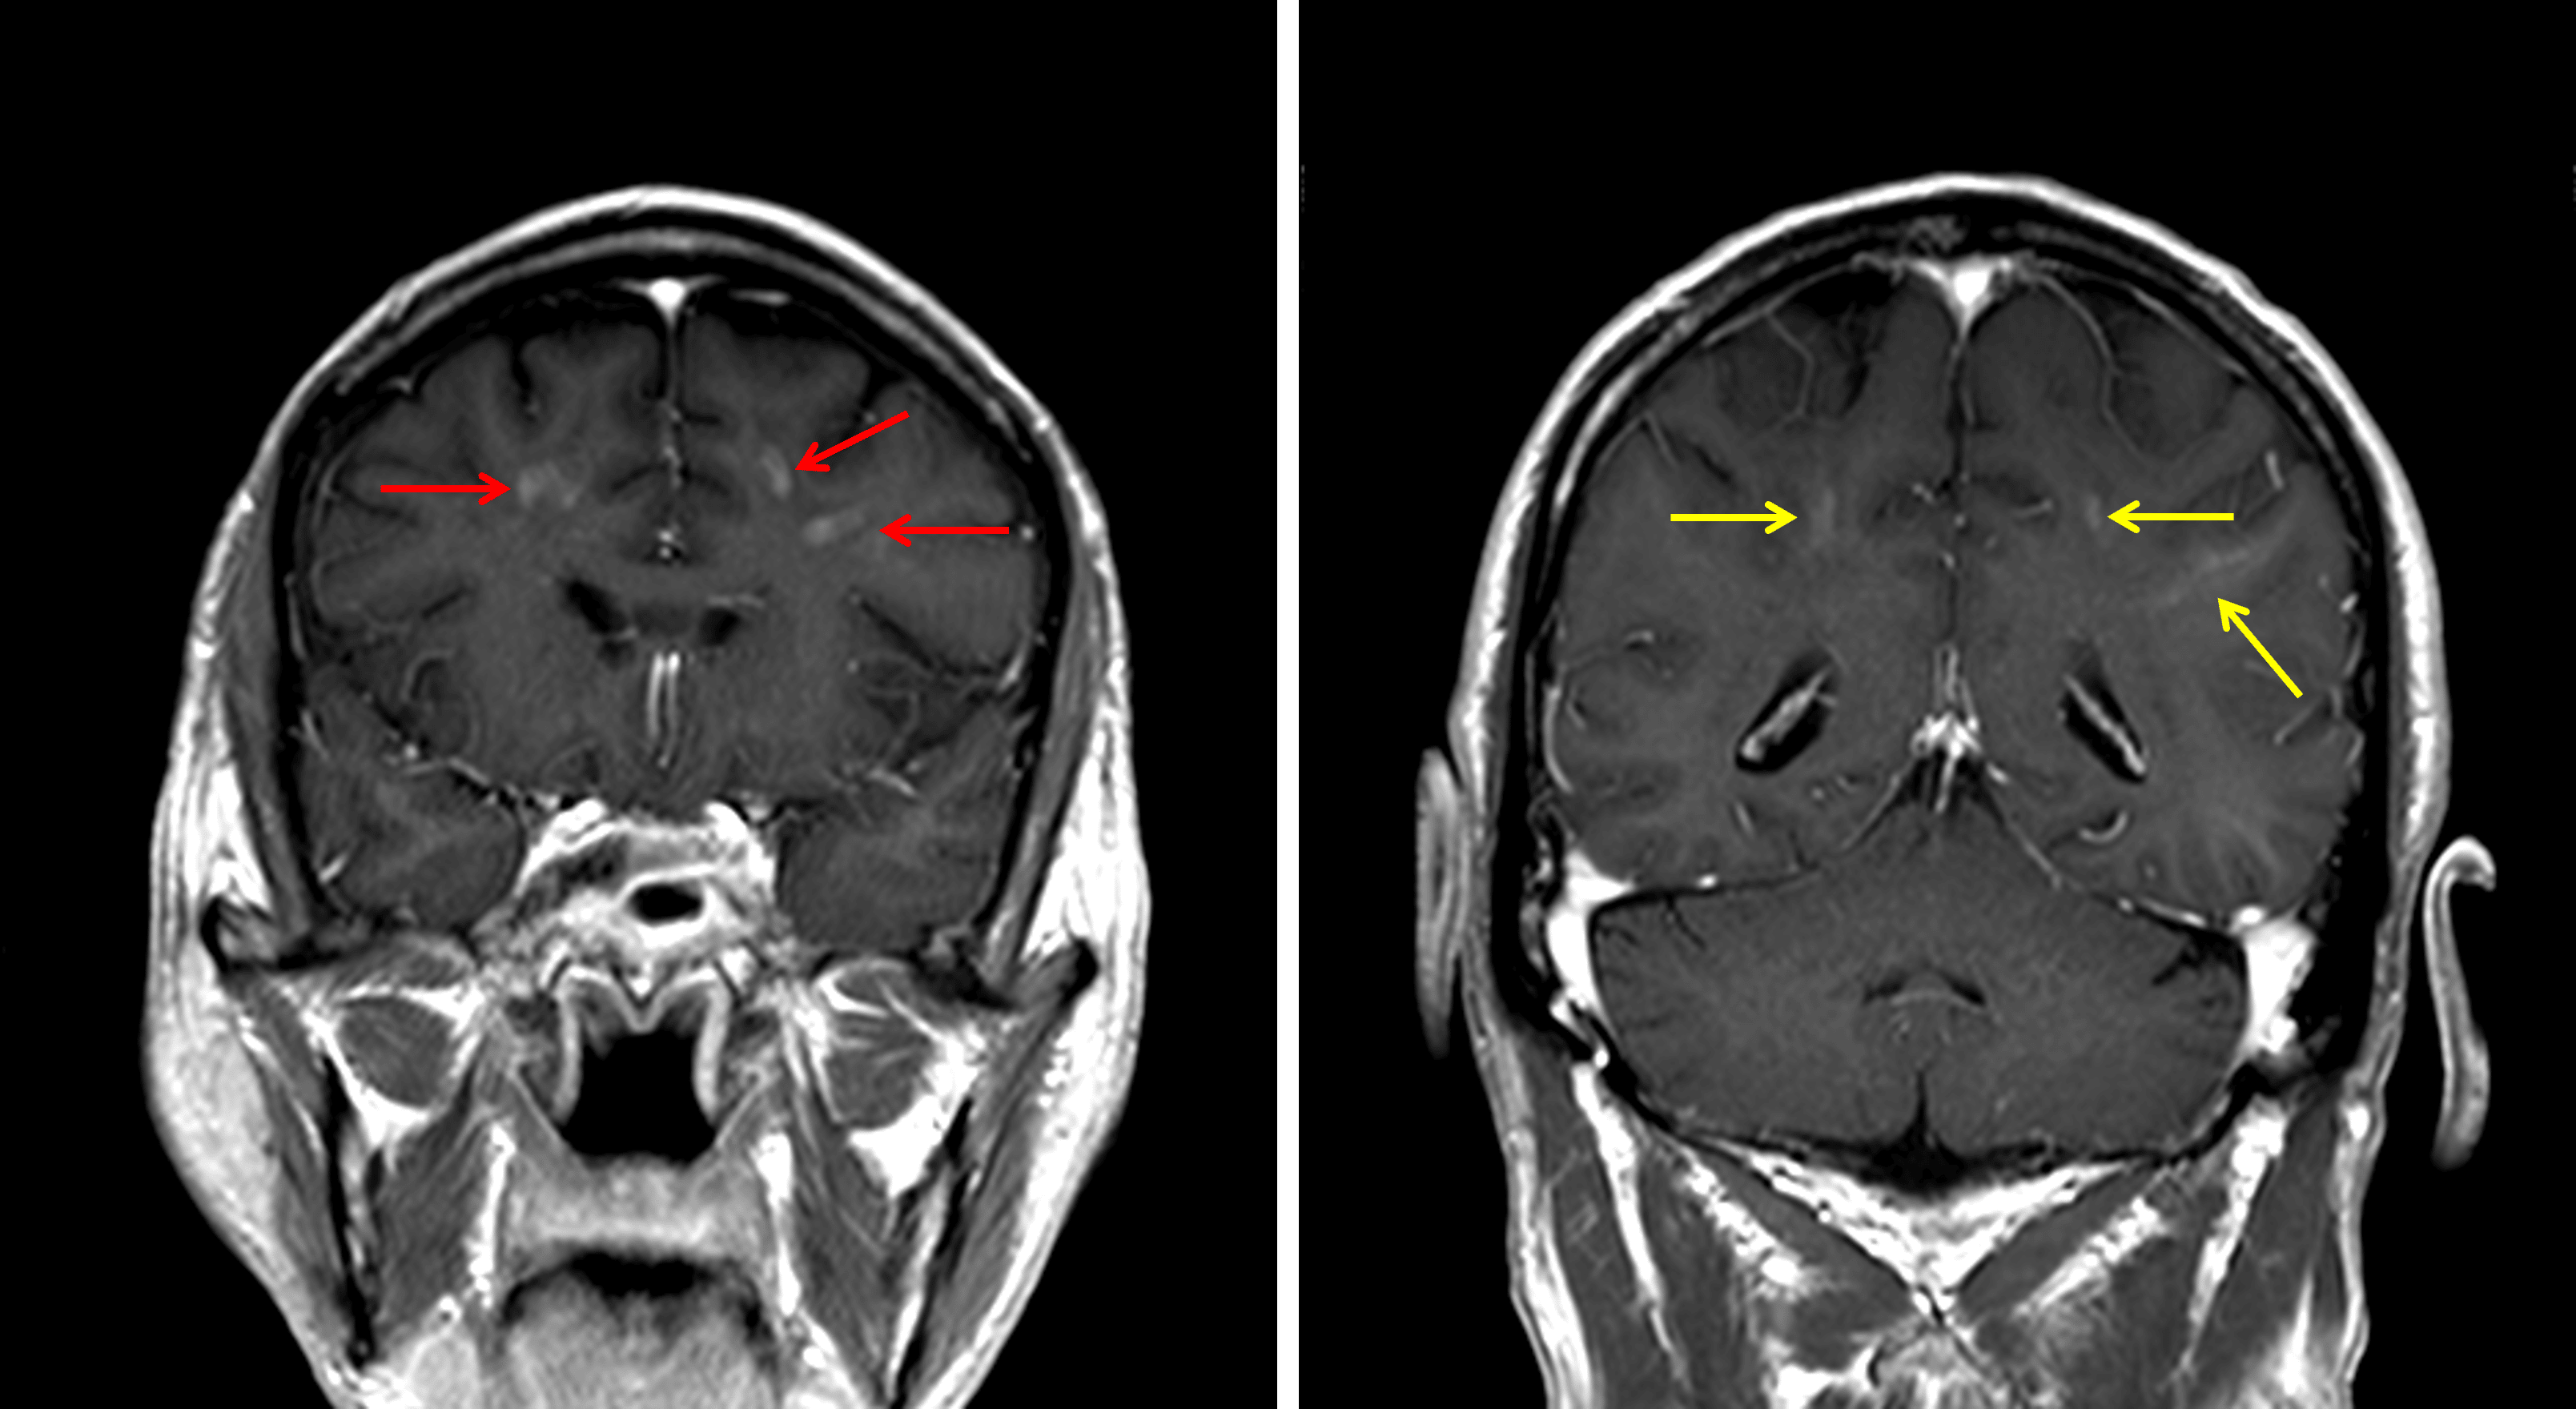

Corresponding areas of enhancement in the frontal lobes (red arrows) and to a lesser extent in the parietal lobes (yellow arrows).

• Corresponding faint linear and nodular areas of enhancement in the bilateral frontal white matter and to a lesser extent in the bilateral parietal white matter